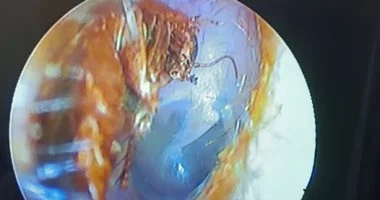

جراح يستخرج صرصور من أذن شاب في القليوبية.. وتحذيرات طبية من خطورة الحشرات